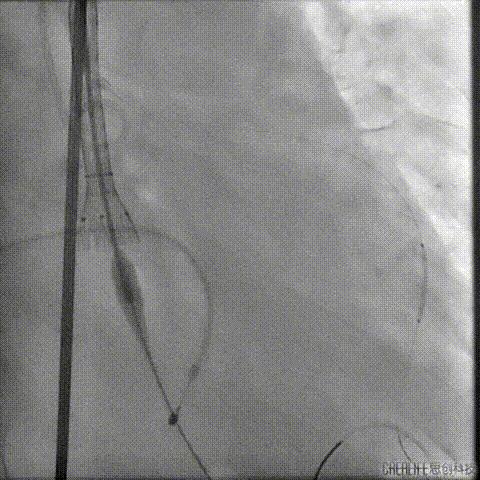

导丝跨瓣及测压

导丝跨瓣后测得跨瓣压差

升主动脉压104/36mmHg

左室压145/15mmHg

跨瓣压差41mmHg

此时患者出现室速 血气提示代谢性酸中毒、高钾血症,予电复率、补碱、补镁、碘氨酮等治疗后恢复窦性心律。